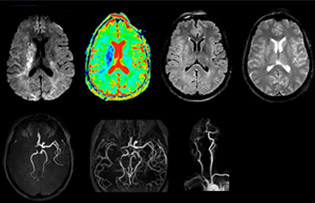

“In France, every stroke is usually imaged with MRI, not CT, even for emergency treatment.” “In France, stroke is usually imaged with MRI, not CT, even for emergency treatment. This is because MRI helps us directly visualize ischemia in the acute phase, but can also help rule out differentials such as MS and hematoma. In addition, we can assess the intracranial and extracranial vessels during the same examination,” says Dr. Savatovsky.

The first challenge in MRI of stroke is speed. The patient typically arrives from an ambulance in the MRI preparation room and the installation is done on a separate dock outside the scanner room. “The venous access is placed during the neurological examination. If the delay from the first symptoms allows the patient to receive thrombolysis we do a very fast examination that typically lasts about 11 minutes including the pre-scans. In the case of transient ischemic stroke we usually add ASL perfusion because in some symptoms with negative diffusion, ASL sometimes indicates a vascular origin.”

“Ingenia provides great flexibility in the parameters setting. We can tune a sequence the way we want,” says Dr. Savatovsky. “For example, in a stroke exam we use a FLAIR sequence of about two minutes instead of the four-minute FLAIR we use for MS. The diffusion is 30 seconds, the T2*-weighted scan is 30 seconds, the angiography scan time is less than one minute. Ingenia is a great scanner in that situation; even with these fast sequences we can achieve good images with good SNR. When the first sequence tells us that it’s not an ischemic stroke but a hemorrhagic stroke, we may switch to a time-resolved angiography to look for vascular malformations and venous thrombosis.

“Every center is different, but for me the ideal protocol for stroke includes diffusion weighted imaging, FLAIR, and fast susceptibility imaging,” says Dr. Savatovsky. “Our fast susceptibility weighted imaging takes 50 seconds, so it’s as fast as T2*-weighted imaging. It visualizes hemorrhage but also the clots. We also do 3D MR angiography that provides information on cervical and brain vessels. If the patient does not need immediate treatment, or if additional information is needed to decide on treatment, we might also add perfusion imaging and post-contrast T1-weighted imaging.”